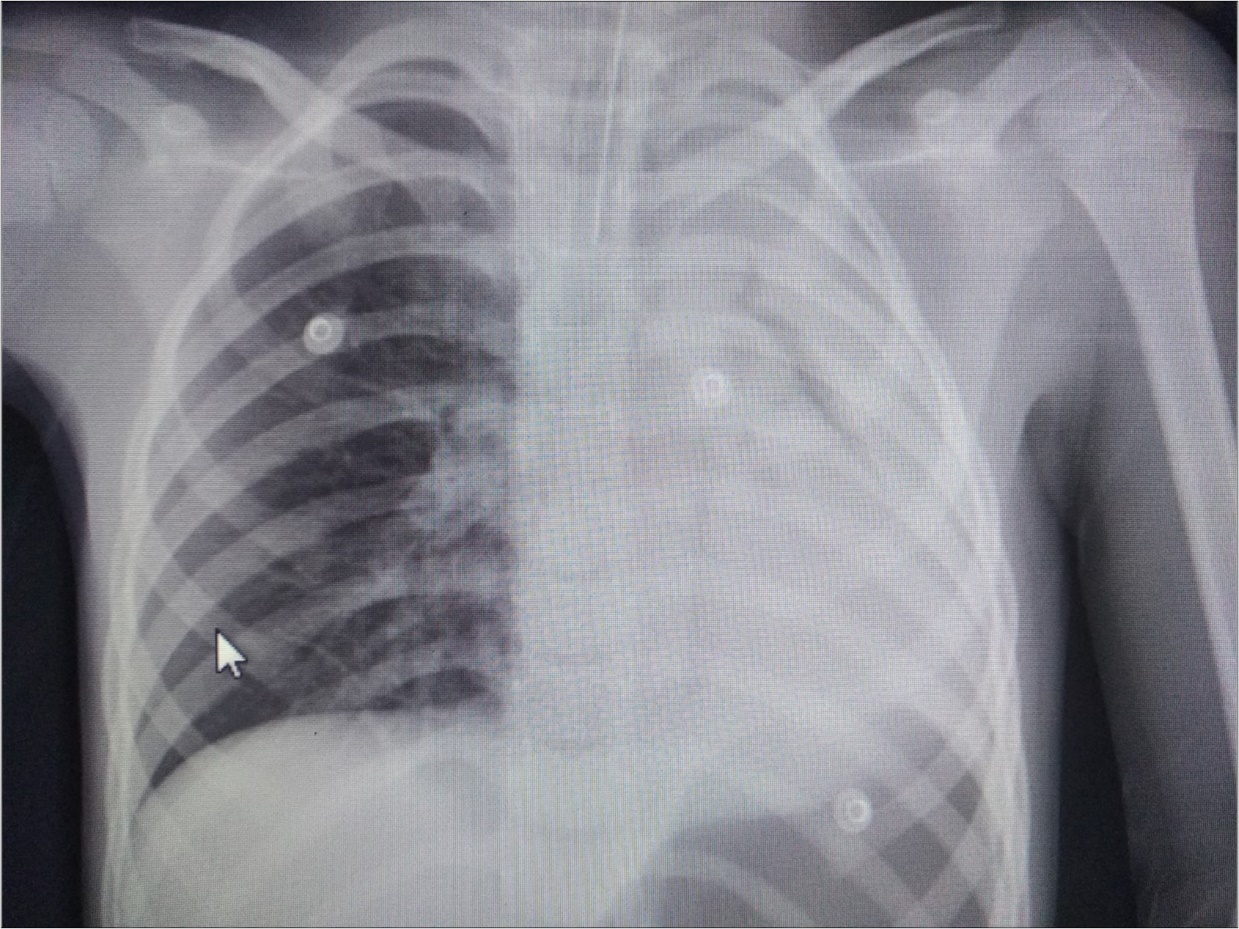

A 6 year-old boy was admitted to our hospital with the symptoms of upper respiratory tract infection (URI). He had hemoptysis 2 days prior to admission to hospital. On admission he had respiratory distress, fever (39°). Plain chest graphy demonstrated a complete opacification of the left lung (Figure 1). Thorax ultrasonography was normal and high resolution computed tomography (HRCT) of the chest revealed a 50-60% narrowing of the left main stem bronchus starting from carina downwards (Figure 2). Although there was no history of foreign object aspiration an emergent bronchoscopy was performed for a possible unnoticed aspirated foreign body. A bronchial cast located at the carineal bifurcation of trachea measuring 3x1 cm was detected and easily removed with forceps during bronchoscopy (Figure 3). The material was whitish, rubbery in consistency. Histopathologic examination of the cast revealed that it consisted of condensed fibrin, neutrophils and eosinophils. Culture was also obtained from the specimen for a possible bacterial growth. Following bronchoscopy the patient required mechanical ventilation for ventilatory support in the mode of high frequency oscillatory ventilation (HFOV) with supplementery oxygen in intensive care unit (ICU). In his 3rd hospital day, control chest graphy of the child showed complete opacification of the left lung and for a chance of residual cast in the tracheobroncial tree a repeat bronchoscopy was performed. Two seperate casts from the left main stem bronchus measuring 1.5x1 cm and 2x1 cm in length were removed with forceps and lavage with aspiration of both right and left main stem bronchus was performed. Following second bronchoscopy the transcutaneous oxygen saturation increased from 77 to 99 and control chest roentgenogram showed equal expension of both lungs. While in his stay in ICU, in addition to mediacal treatment, respiratory physiotherapy was performed regularly. He was medically treated with aerosolized dexamethasone with adrenalin. Bacterial test obtained from cast was found positive for Streptococcus viridans and vancomycin was started. On his 5th day in ICU, his respiratory status worsened and a chest graphy showed a decrease in expension of the left lung and a control bronchoscopy was performed. In this third bronchoscopy trachea and both right and left main stem bronchus were found to be patent but were found to have excessive viscous secretions. Pulmonary toilet including lavage and aspiration of thick tenacious secretions was performed. On day 12 he was transferred from the ICU and 1 week later he was weaned off the ventilator. He underwent pulmonary rehabilitation. During his 3rd year of follow up he has no further episodes of respiratory distress and he is disease free.

Figure 1.Chest radiograph showing left-sided opacification.

Radiographic findings are nonspecific and include atelectasis secondary to airway obstruction, hyperinflation due to air trapping, unilateral opacification, as seen in our case, bronchiectasis and lung infiltrates. It has been reported that HRCT may allow in some cases the visualization of bronchial casts in the airways of larger caliber 19. However the gold standard in diagnosing PB is bronchoscopy which reveals the airway obstruction by BC 3.